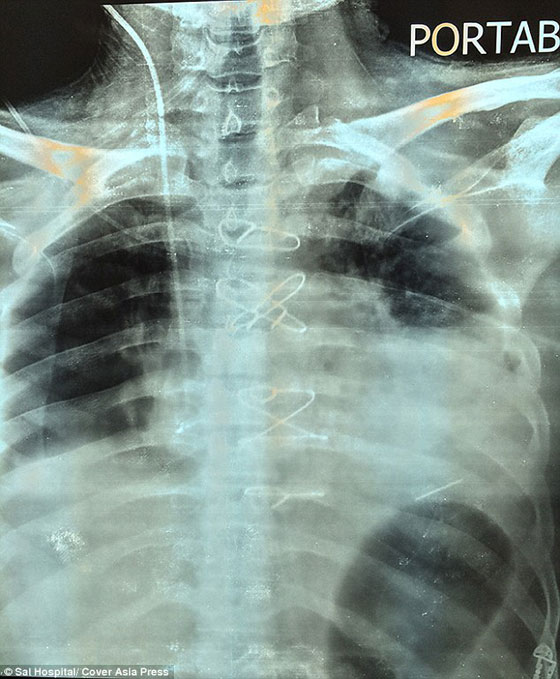

غير أن شارما اضطر الثلاثاء إلى السفر إلى أحمد أباد غربي الهند للخضوع لعملية جراحية لإزالة الرصاصة من قلبه في مستشفى سال الخاص. وكانت العملية معقدة للغاية جراء استقرار الرصاصة في الجزء الأسفل من القلب، بالقرب من البطين الأيسر، بحسب ما نقلت صحيفة الغارديان البريطانية.

وأكد الجراح في مستشفى سال، أنيل جاين، أن العملية الجراحية استغرقت زهاء 3 ساعات لإزالة الرصاصة، موضحاً أنها "استقرت بشكل أفقي بين الصمامين". وأضاف: "ولأن المريض فقد الكثير من الدم بعد الحادث، كان لزاماً علينا أن نكون حذرين للغاية، أما كيف عاش المريض لهذه الفترة ووصل إلينا فكله محض قدر". وقال الجراح إن شارما سيتمكن من العودة إلى العمل في غضون شهر، وهو يرقد حالياً في وحدة الرعاية المكثفة في المستشفى.